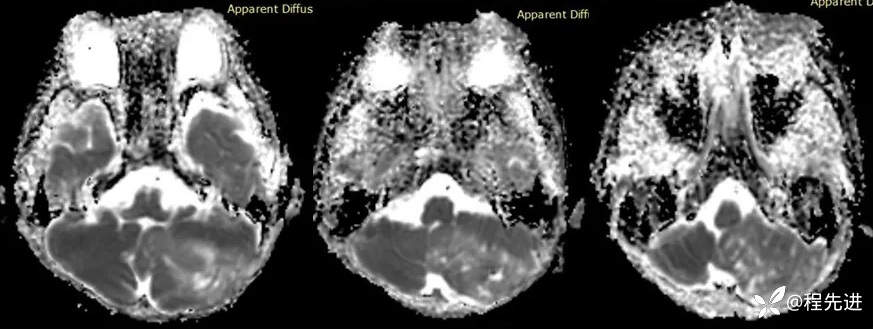

【患者信息】:男,6岁

【主诉】:查体发现左侧小脑半球占位3个月

【现病史及既往史】:患者3个月前因鼻塞至外院就诊,行头颅CT检查偶然发现颅内占位

【检查】